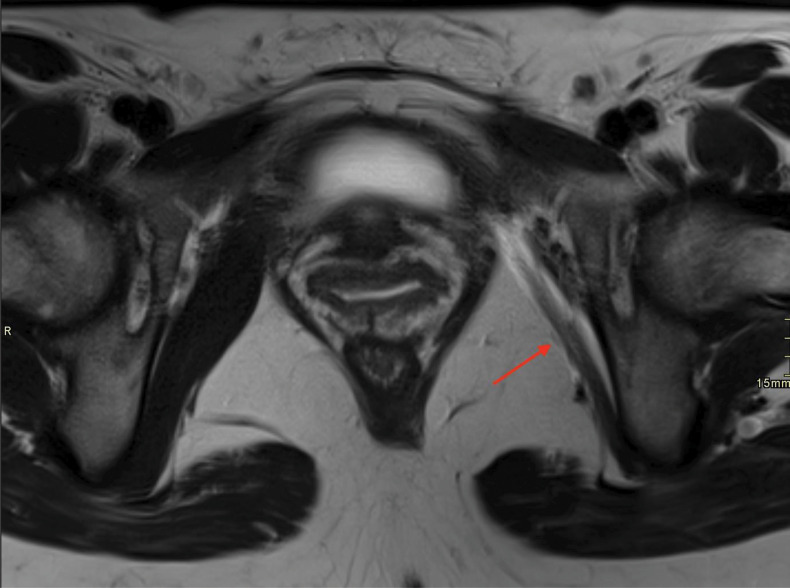

Extrapelvic Endometriosis Involving Pudendal and Sciatic Nerve Causing Obturator Muscle Atrophy.

Teaching point: Extrapelvic endometriosis involving pudendal and sciatic nerve may be a cause of lower limb pain.